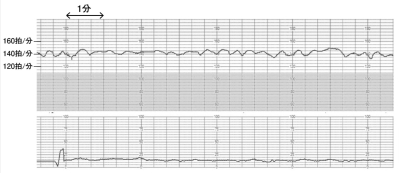

36歳の初産婦。妊娠29週。胎動減少を主訴に来院した。妊娠初期の血液検査で抗D抗体陽性(抗体価16倍)だったため経過観察されていた。妊娠27週の時点で抗 D 抗体が 1,024 倍であったが胎児超音波検査で異常を認めなかった。16年前、妊娠初期に人工妊娠中絶手術を受けている。輸血歴はない。胎児心拍数陣痛図を別に示す。

対応として適切なのはどれか。2つ選べ。